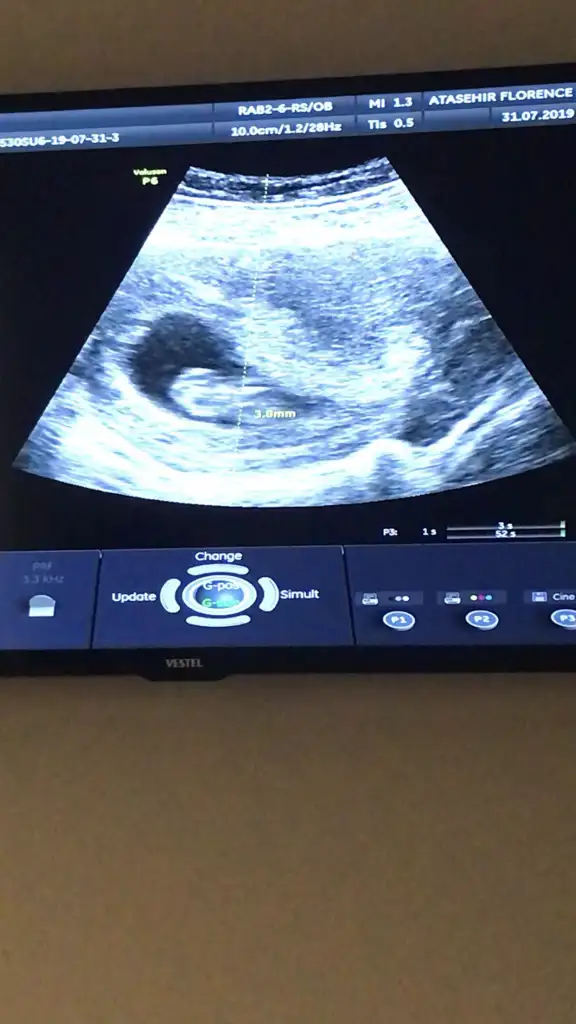

Bakalım cinsiyetlerde aynı olacak mısat ve kilo uymuyor diğerleri aynı![]()

Yok 24 benimki geçen hafta gittim bende ama daha kol bacak çok belli değildi hareket ettimi resmi varsa atar mısın en azından benimkine benziyor diye bakardım

Maasallah Allah sağlıkla kucağına almayı nasip etsin hayırlı evlat olsun inşallahAaa 1 gün var aramızda süpervideodan fotosunu çektim yükliyim,hareket edıyodu yüzüyor gibi

kollarını bacaklarını gördüm . Bayramdan sonraki hafta 2 li test yapıcak ozama cinsiyeti söylerim dedi

Sadece ense ölçümünü not almış 1 olarak ölçmüş. Gebelik haftanı not almış şimdilik önemli bişey yok kan sonucun çıkınca oranlanacak :)Merhaba kızlar kontrolum vardi bugün doktor herşey normal dedi çok şükür. Zipliyordu eli kolu durmuyordu zor ölçtü hocaCinsiyet için bir ay sonra kesinlessin o zaman söyleyim dedi. ikili için kan verdim tsh t4 icin de sabah kan vericem. Sonuç raporunu koyuyorum buraya bilgili arkadaşlardan yorum alırım.